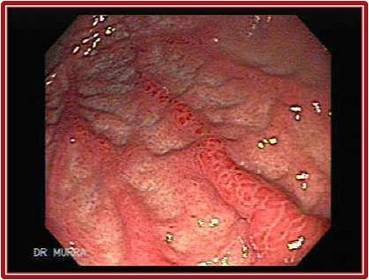

GASTRITIS EROSIVA

“Gastritis “erosivas y hemorrágicas, las causas más comunes son:       Medicamentos (AINES) Estrés Gastropatía hipertensiva portal, (asociada a la presencia de Hipertensión Portal)